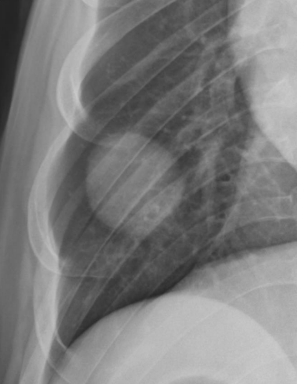

Alveolar pattern

• ์–ธ์ œ?

• ๋ฌด๊ธฐํ, ํ๋ ด,. .

• ์ƒ๋ช…๊ณผ ๊ด€๋ จ ์žˆ๋Š” ์งˆ๋ณ‘๊ณผ ๋ฐ€์ ‘ํ•˜์—ฌ, ๊ฐ€์žฅ ์ค‘์š”

• perihilar region์—์„œ pattern

• ๊ณ ์–‘์ด : ์ „๋ฐ˜์ ์œผ๋กœ ์ง€์ €๋ถ„ํ•˜๊ฒŒ ์ฐฌ ๋ชจ์Šต

• ๊ณ ์–‘์ด ํ์ˆ˜์ข…์˜ ์ „ํ˜•์  : ์ข€ ์ง€์ €๋ถ„ํ•˜๊ฒŒ ๋‚˜ํƒ€๋‚จ, ๋‹ค๋ฅธ ํŒจํ„ด๊ณผ ํ—ท๊ฐˆ๋ฆผ

• ํ๊ฐ€ ์ชผ๊ธ€์–ด๋“ค์–ด

• ์˜ค์—ฐ์„ฑ ํ๋ ด (